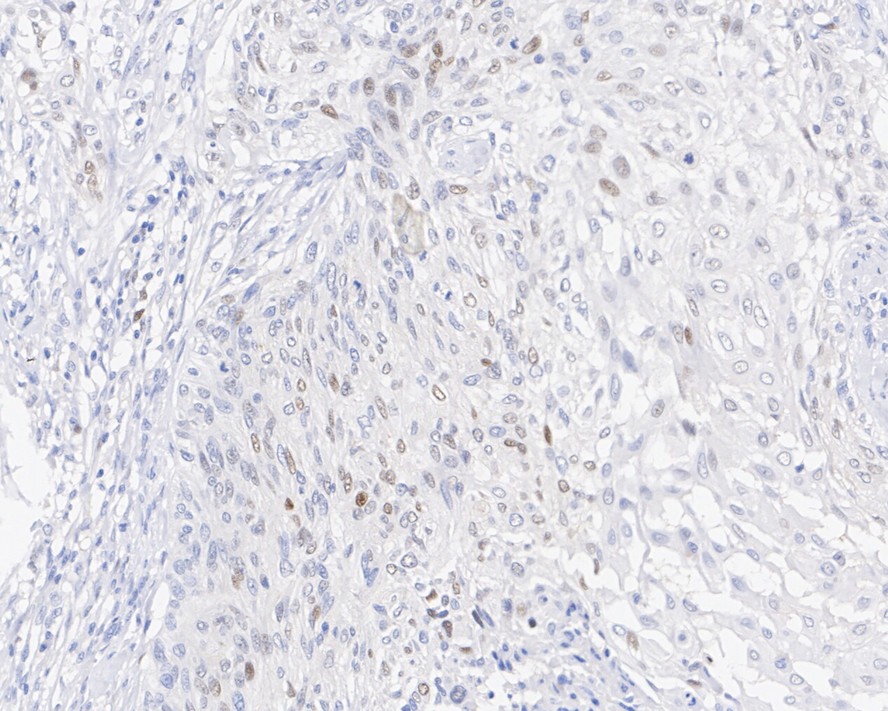

p21 Recombinant Mouse Monoclonal Antibody [A8C11-R]

IHC-P

Human